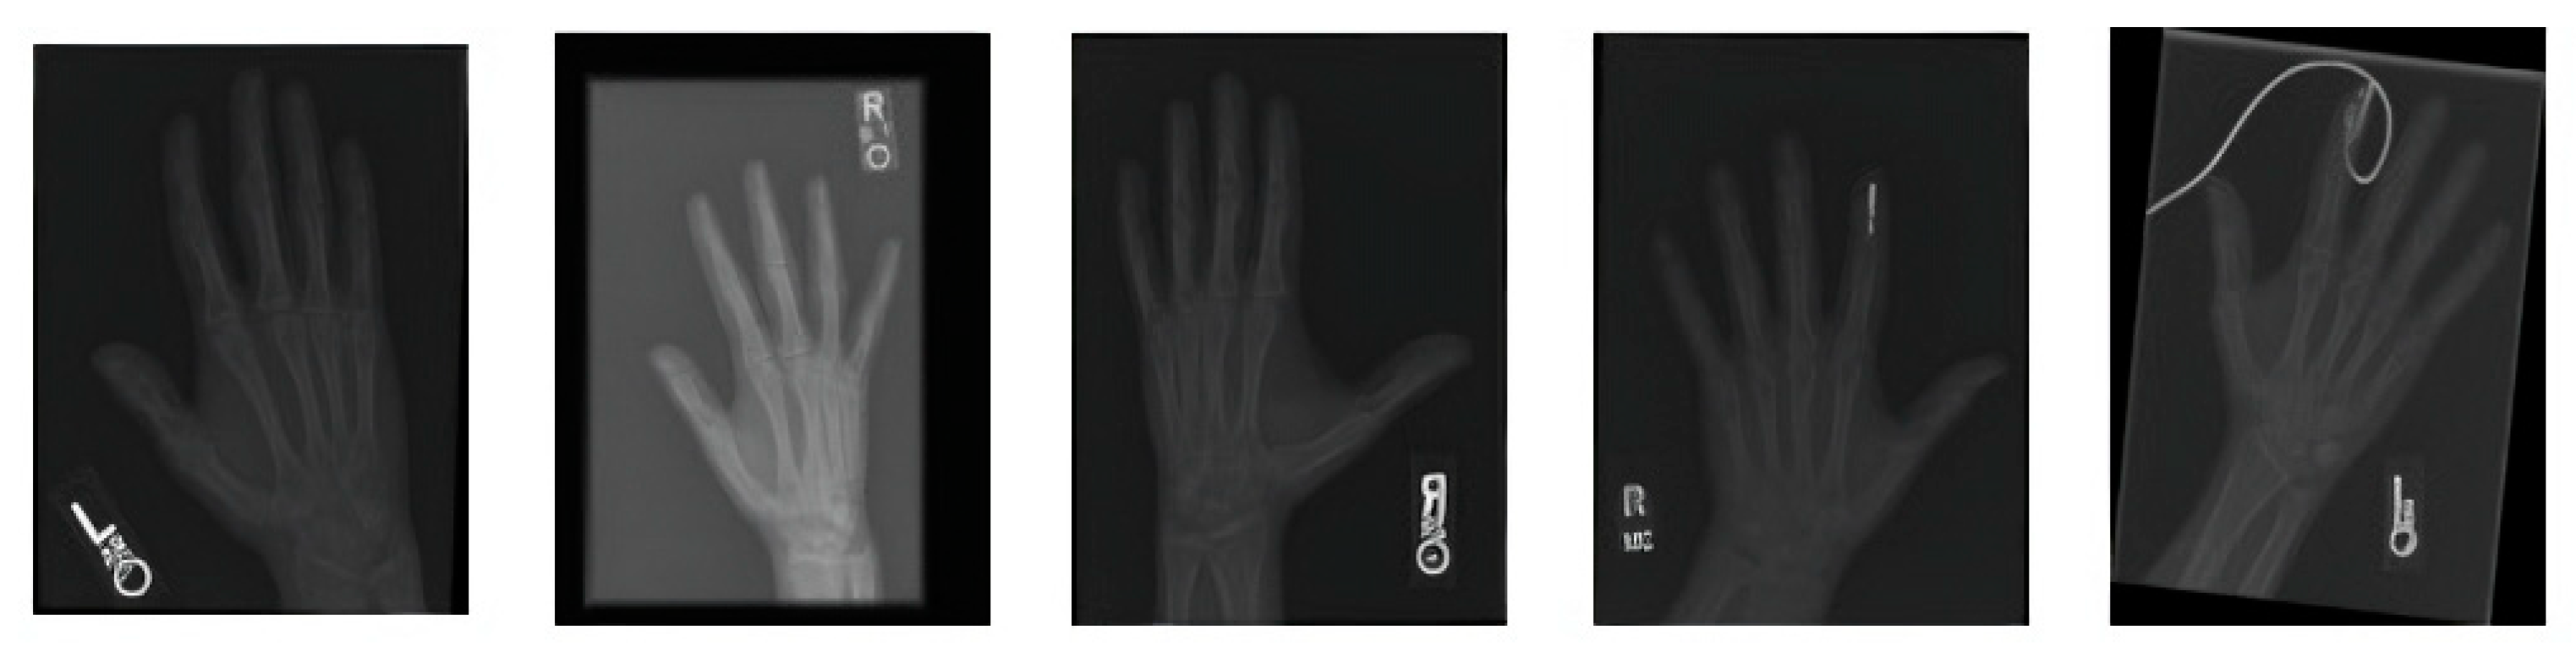

Figure 3 shows the segmentation of carpal bones of the wrist by hand X-ray images. The original hand image with its original black structure is the input; then, the application of global thresholding followed to constitute a binary mask. This thresholding technique demonstrated the capability of distinguishing the bone tissue from the background. Then, after all the bones had been segmented, contours were drawn that indicate the borders of the carpal bones. This visual representation enables the doctor to have a better understanding of the internal structures of the wrist.

Figure 3. A sample of images after segmentation of carpal bones.